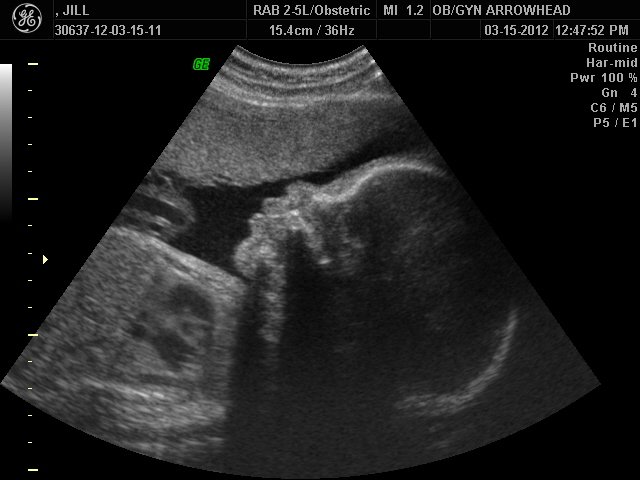

We offer complimentary 3D/4D Ultrasounds to all our OB patients around 30 weeks! The following photos are some examples of our work, shown with permission from our patients.